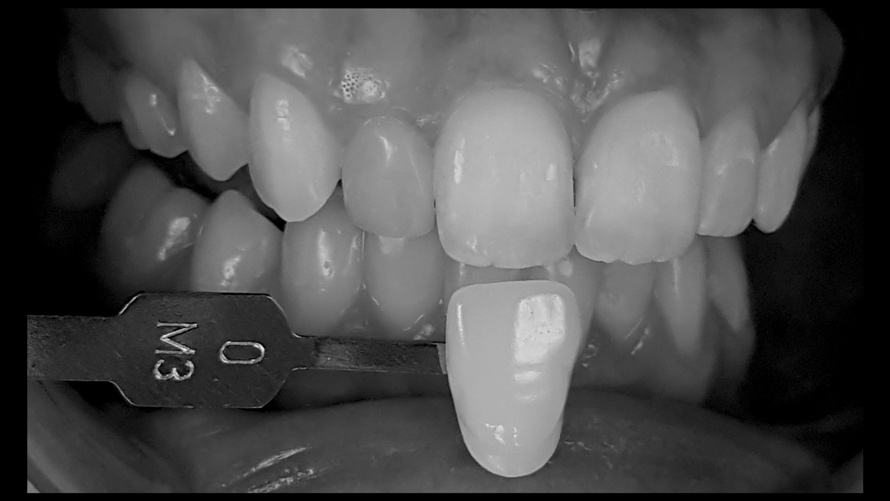

Shade Selection and Laboratory Communication

The most utilized intraoral photographs in the field of dentistry are perhaps those that capture shade information (Figure 18 and Figure 19). The analysis of color (ie, value, chroma, hue) in dentistry is a critical step in the fabrication of esthetic indirect restorations, such as all-ceramic crowns and porcelain laminate veneers. The ability to properly communicate this information with the dental laboratory is essential to ensure an appropriate shade match, a reduction in chairtime and overhead, and most importantly, a satisfactory patient experience and treatment outcome. In recent years, the use of polarized light photography as an aid in the shade selection process has become extremely popular. For some EALS devices, special polarizing filters have been specifically designed to fit over the light-emitting portion of the device (Figure 20 and Figure 21). The images produced using polarized light photography demonstrate an elimination or reduction in the specular reflection of hard and soft tissue, resulting in a matte-finish appearance of the dentition and gingiva. These types of photographs aid the ceramist in identifying areas of opacity and translucency, crack lines, hypo- or hypercalcification, and other internal features of the dentition that may not be readily visible without such a filter (Figure 22).

(18.) Tooth shade analysis of value, chroma, and hue taken with a smartphone and an EALS device.

Figure 18

(19.) Tooth shade analysis of value, chroma, and hue taken with a smartphone and an EALS device.

Figure 19